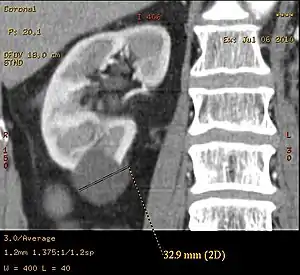

Renal ultrasonography of a simple renal cyst with posterior enhancement.

A very small (8 mm) simple renal cyst.

Bosniak II cyst at the lower pole of right kidney with septations within.